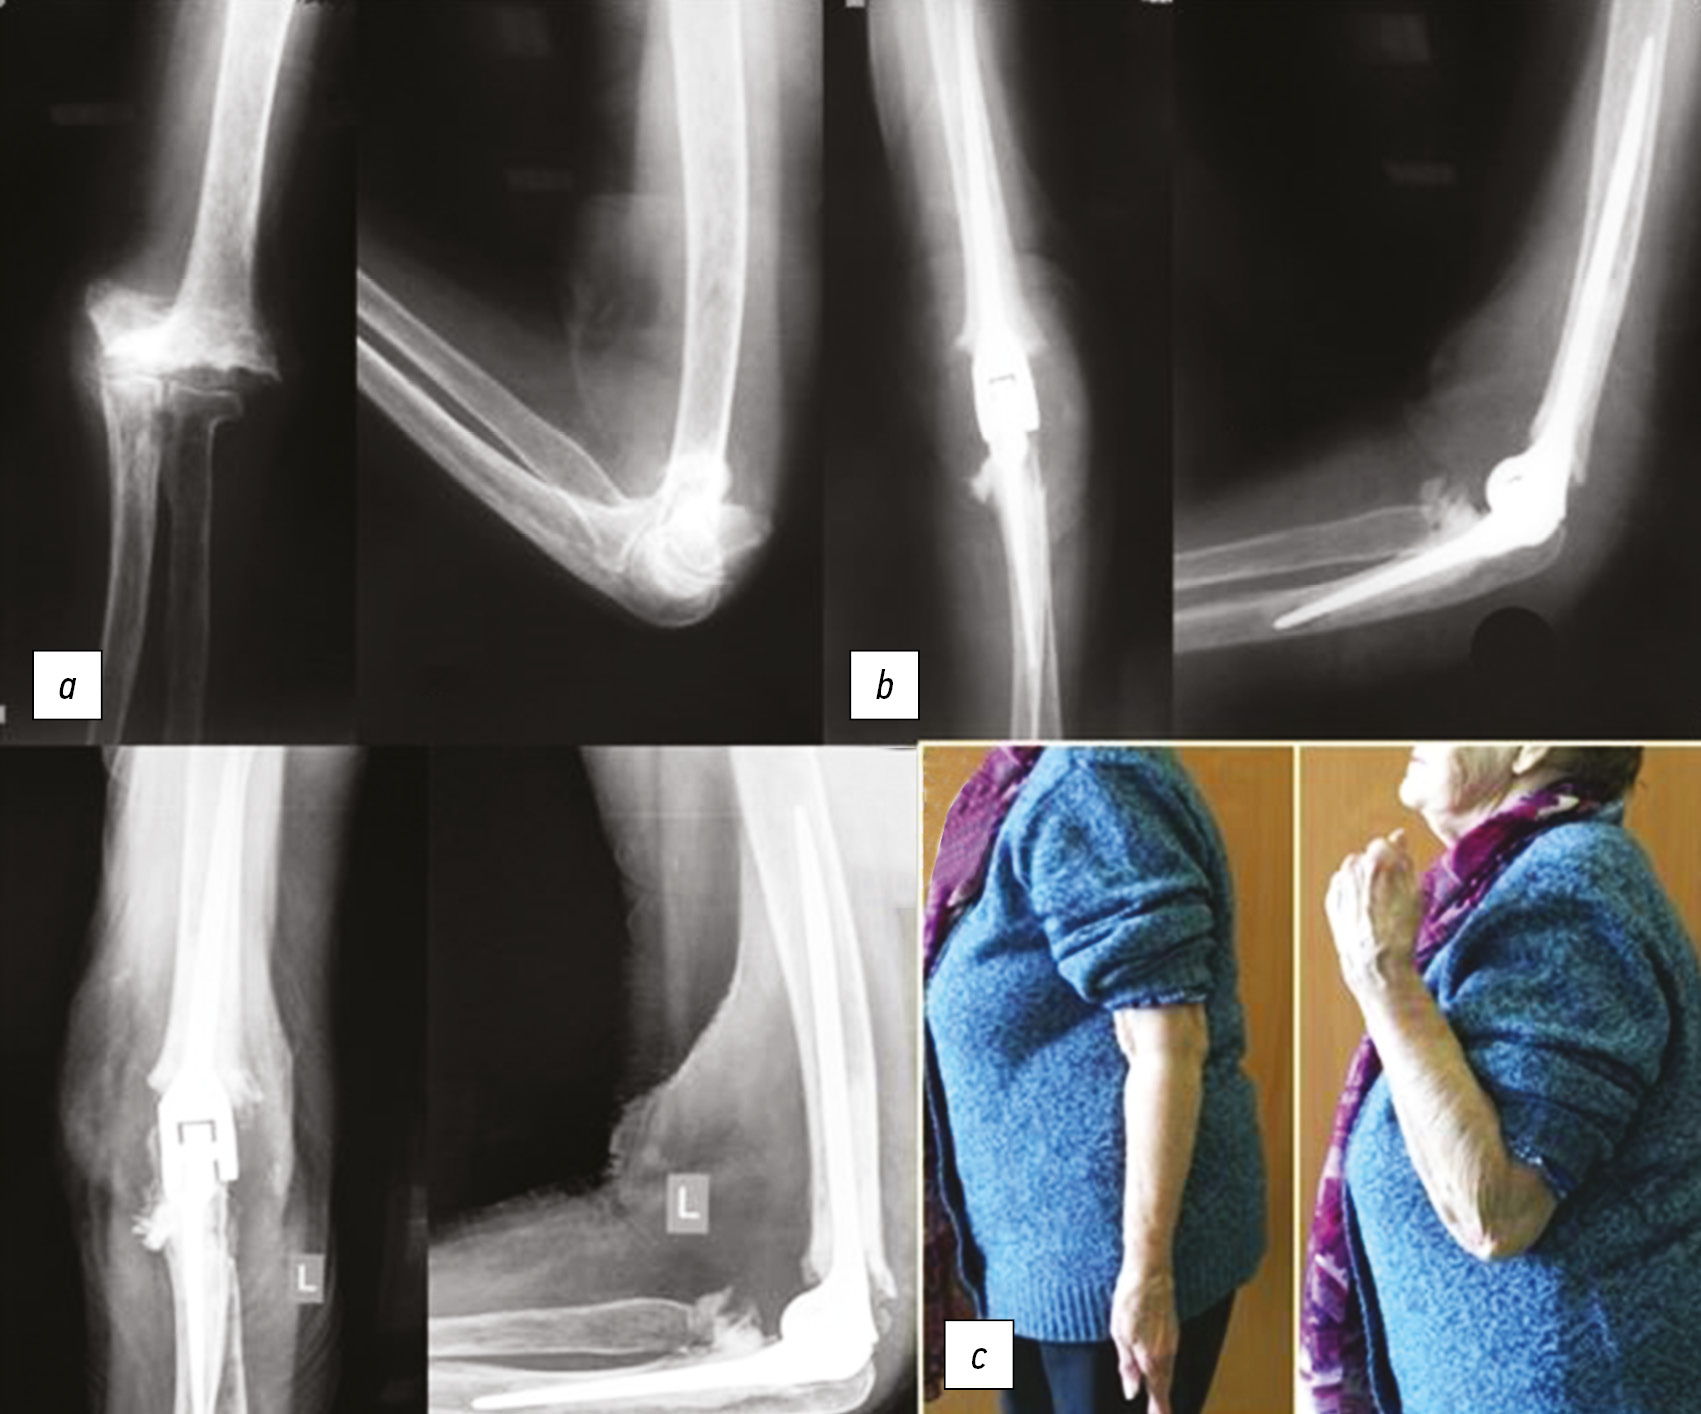

Клинический пример № 2. Пациентка 70 лет, чрезмыщелковый перелом плечевой кости, 2 года после травмы и консервативного лечения в гипсовой повязке в течение 2 мес. После снятия повязки назначен курс ЛФК, однако стали прогрессировать боли и нестабильность в локтевом суставе из-за сформировавшегося ложного сустава мыщелка плеча (рис. 4, а). Больной выполнено тотальное эндопротезирование локтевого сустава эндопротезом «ЭСИ» (рис 4, b). В дальнейшем проведен курс реабилитационного лечения. Больная осмотрена через 1,5 года после операции, объем движений в локтевом суставе удовлетворительный, болевой синдром не выражен (рис. 4, с).

Рис. 4. Пациентка, 70 лет: a — рентгенологическая картина при поступлении; b — выполнено тотальное эндопротезирование сустава; c — результат лечения (1,5 года после операции)

Fig. 4. Patient, 70 years old: a — X-ray picture upon admission; b — total joint replacement was performed; c — the result of treatment (1.5 years after surgery)